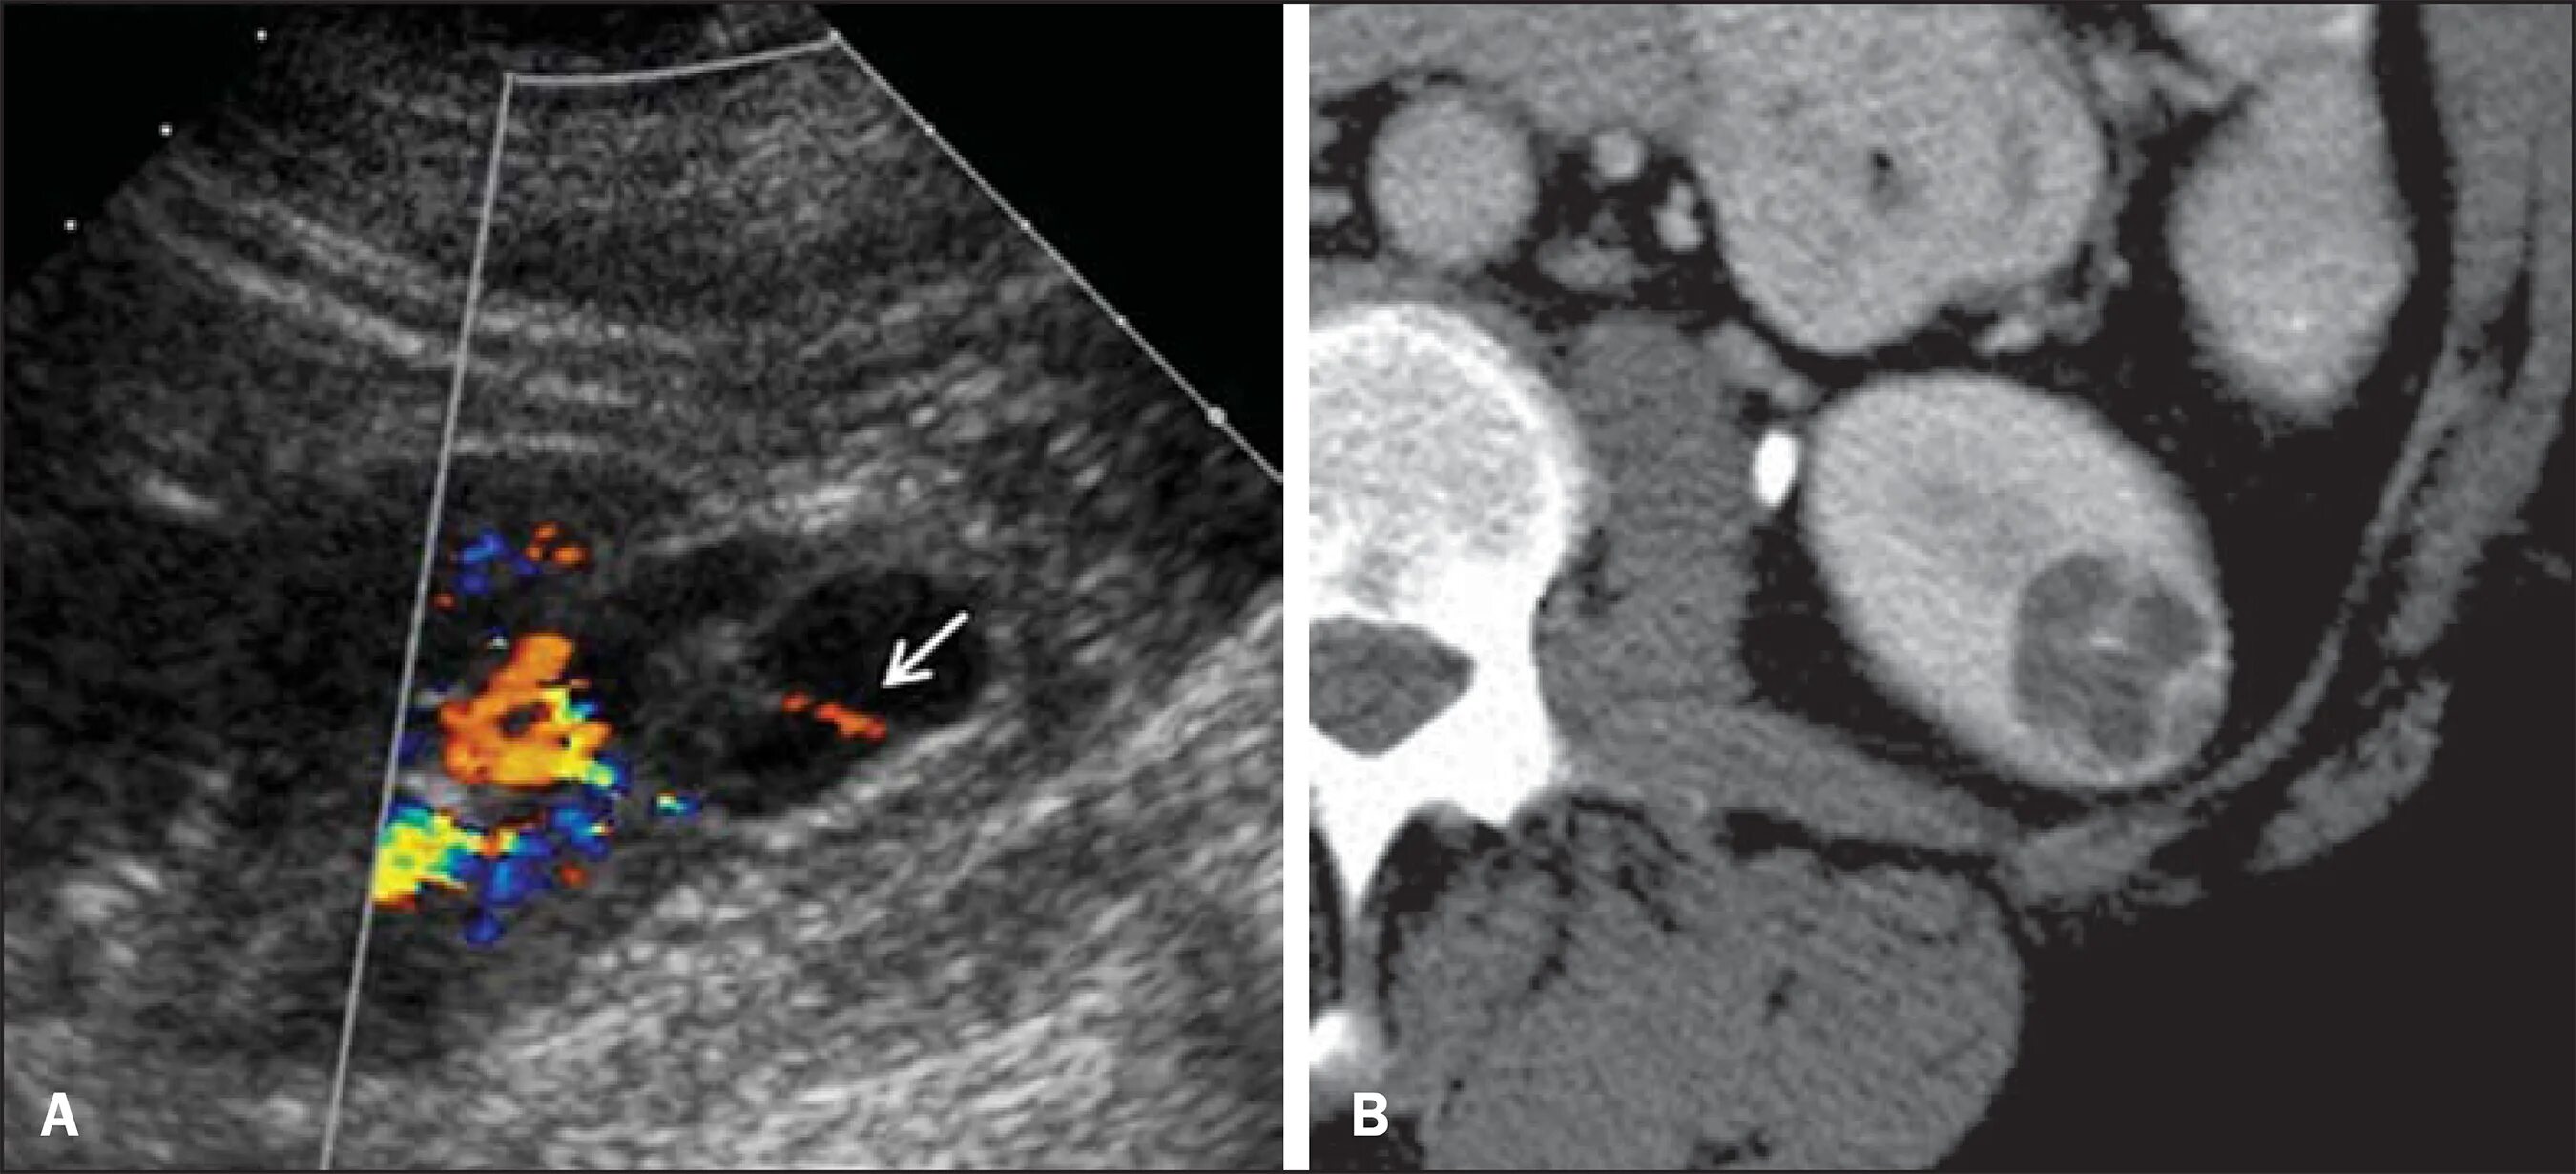

Можно вылечить кисту почки